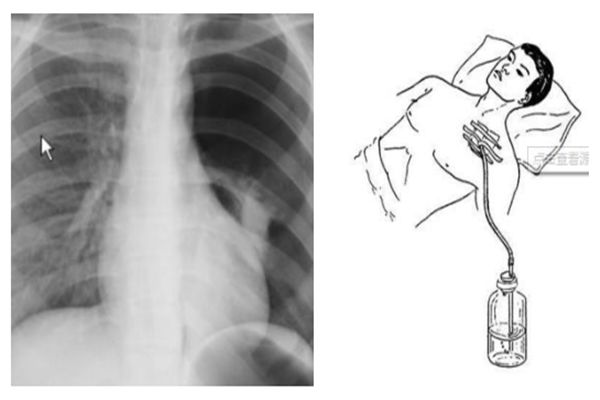

8. 气胸

气胸是锁骨下静脉穿刺中最常见的并发症之一,通常是由于穿刺时针头刺入过深,即针头与胸壁表面成角太大,误入胸腔而引起。最早的临床表现是咳嗽,一旦怀疑患者有气胸,必要时需要拍摄直立位的X线片确诊。

小量气胸不需特殊处理,少数严重的张力性气胸,通常采用闭式引流进行处理。

图8. 气胸。